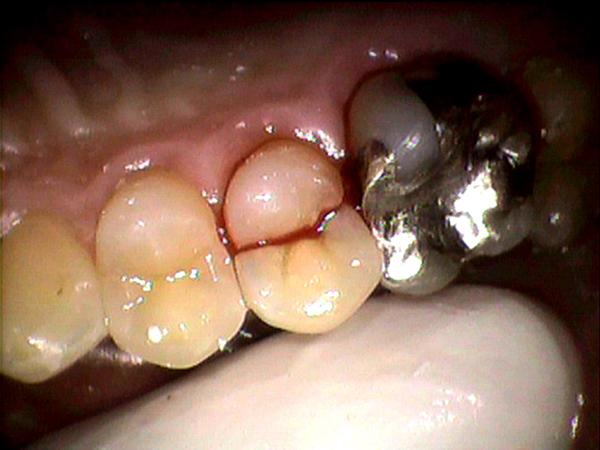

③歯周病が進行しやすくなる

銀歯の表面は傷がつきやすく、小さい傷に口の中の歯周病菌がくっつきやすくなります。

銀歯と歯茎の境目には歯周病菌他たくさんの菌がたまりやすい状態であり

銀歯を入れると歯周病の進行し悪化しやすくなります。